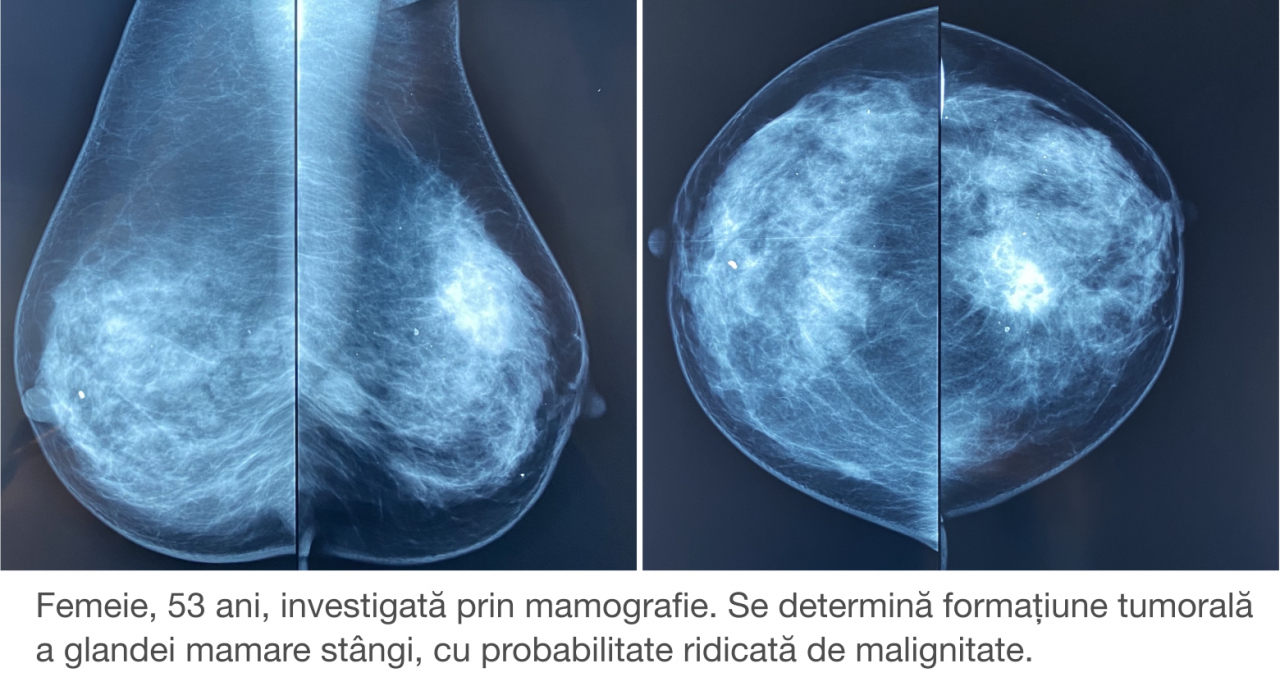

УЗИ молочных желез в Москве

УЗИ молочных желез — информативный и безопасный метод диагностики, с помощью которого можно точно оценить состояние желез, обнаружить доброкачественные и злокачественные образования, уточнить диагноз. Это доступное по цене исследование безвредно и не несет лучевой нагрузки. Оно имеет большое значение в ранней диагностике заболеваний и нередко применяется в профилактических целях. На УЗИ может направить маммолог, онколог, эндокринолог, гинеколог.

Сделать УЗИ молочных желез можно в качестве первичной диагностики и для уточнения уже предполагаемого диагноза. Метод основывается на способности высокочастотных ультразвуковых волн с различной скоростью отражаться от тканей с разной плотностью.

С помощью ультразвуковой диагностики можно обнаружить следующие заболевания:

- воспалительные заболевания — мастит, абсцессы, лактостаз у кормящих женщин, мастопатии различного происхождения и типа — фиброзно-кистозные, диффузные и пр.;

- врожденные аномалии молочной железы;

- рак;

- кисты и доброкачественные опухоли;

-

кальцинаты.

Для оценки кровотока в тканях молочных желез используется доплерография. Данные, полученные в результате биопсии под контролем УЗ-аппарата, могут сказать о природе и характере образований в молочных железах.

Кому противопоказано

УЗИ практически не имеет противопоказаний. Однако важно отметить, что информативность обследования груди таким способом у женщин молодого возраста выше, поскольку ткани молочных желез с возрастом становятся более рыхлыми. Поэтому после 40 лет УЗИ в большинстве случаев сочетается с рентген-диагностикой (маммографией).